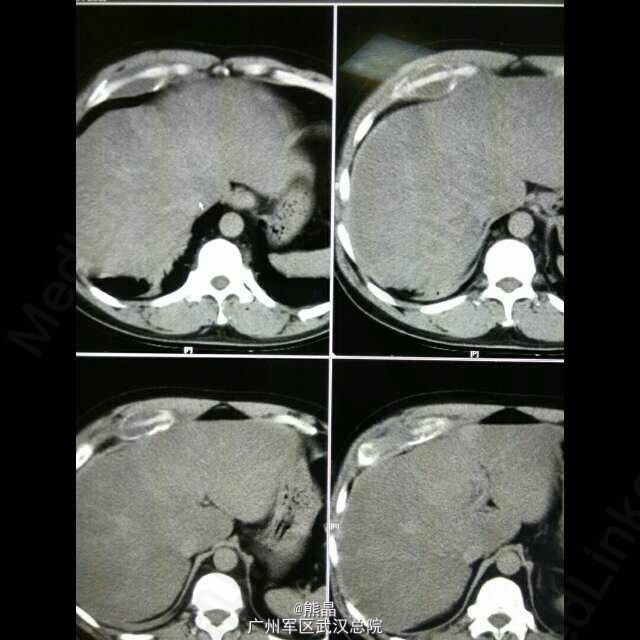

肋软骨脓肿

病史:患者男性,38岁,半年前出现右侧胸部疼痛,逐渐加重。 CT三维重建提示右第7、8肋软骨炎伴肋骨部分坏死溶解。